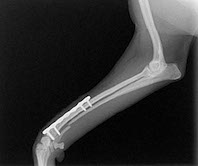

超がつく小ささの前肢の骨折です。

写真だと拡大しているので分かりづらいですが、体重がなんと1kg!両手のひらに乗る大きさで、ネジを打ち込む骨の幅が3.1mmしかありません。5円玉の真ん中の穴ですら4.8mmくらいあります。ちょうど100円玉2枚重ねた厚さと同じくらいです。

現在使用できるロッキングプレート&ネジの最小の物でギリギリです。

関節に近いところが折れているため大変です。

トイプードル、ポメラニアン、ヨークシャーテリアなどの小型犬では写真の様に前足が折れやすいです。

昔はピンを入れたり、DCP等のプレートを挿入して治療していましたが、最近はチタン製のロッキングプレートを用いての治療が主流です。

これまた小型犬の橈尺骨の骨折です。関節に近い場所なので固定が難しいです。